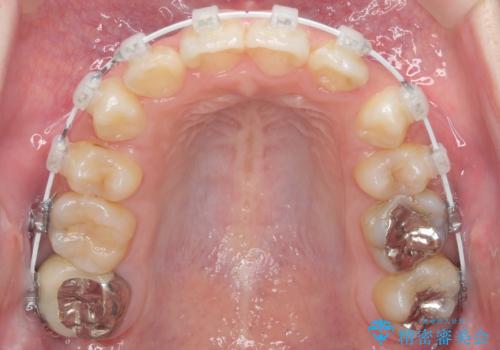

- ワイヤー矯正

- 3年1ヶ月

- 前歯のがたつきを主訴に来院。

顔が小さく、顎に大きな歯が入りきらない状態でした。

抜歯してワイヤー矯正を行いました。